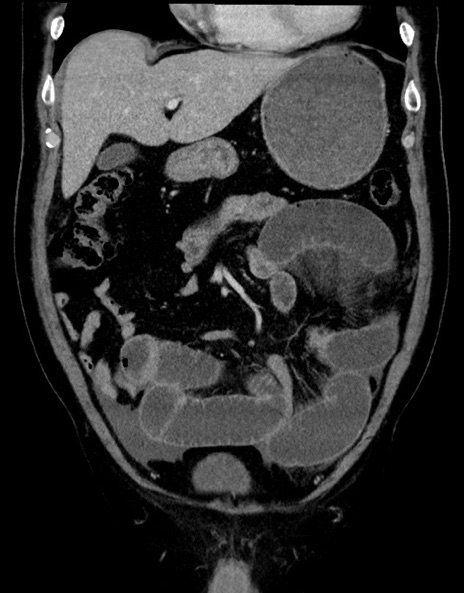

症例15(冠状断像)

【症例】70歳代男性

【主訴】腹痛

【現病歴】今朝から腹痛あり。全体的に痛い。特に左上の方。排ガスが今日はない。冷や汗が出る。

【既往歴】直腸癌術後

【身体所見】左側腹部〜上腹部に圧痛あり。腹膜刺激症状明らかなではない。軽度反跳痛。左下腹部に術後瘢痕あり。

【データ】WBC 7700、CRP 0.02